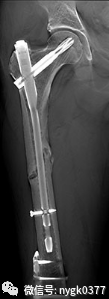

视金识功能去金属伪影功能

基于断层融合图像,智能提取金属假体,把金属假体与骨骼图像有效的区分及组合。使金属假体与骨科图像均可以清晰显示。在视金识图像上即可以清晰的观察金属假体又可以细致的分析假体与骨骼之间的关系。对关节置换术后恢复的观察,翻修术的术前分析起到了有效的影像支持。

岛津有哪些影像设备岛津 C200拥有性能完善的影像链系统_https://www.jmylbn.com_新闻资讯_第11张

岛津有哪些影像设备岛津 C200拥有性能完善的影像链系统_https://www.jmylbn.com_新闻资讯_第12张